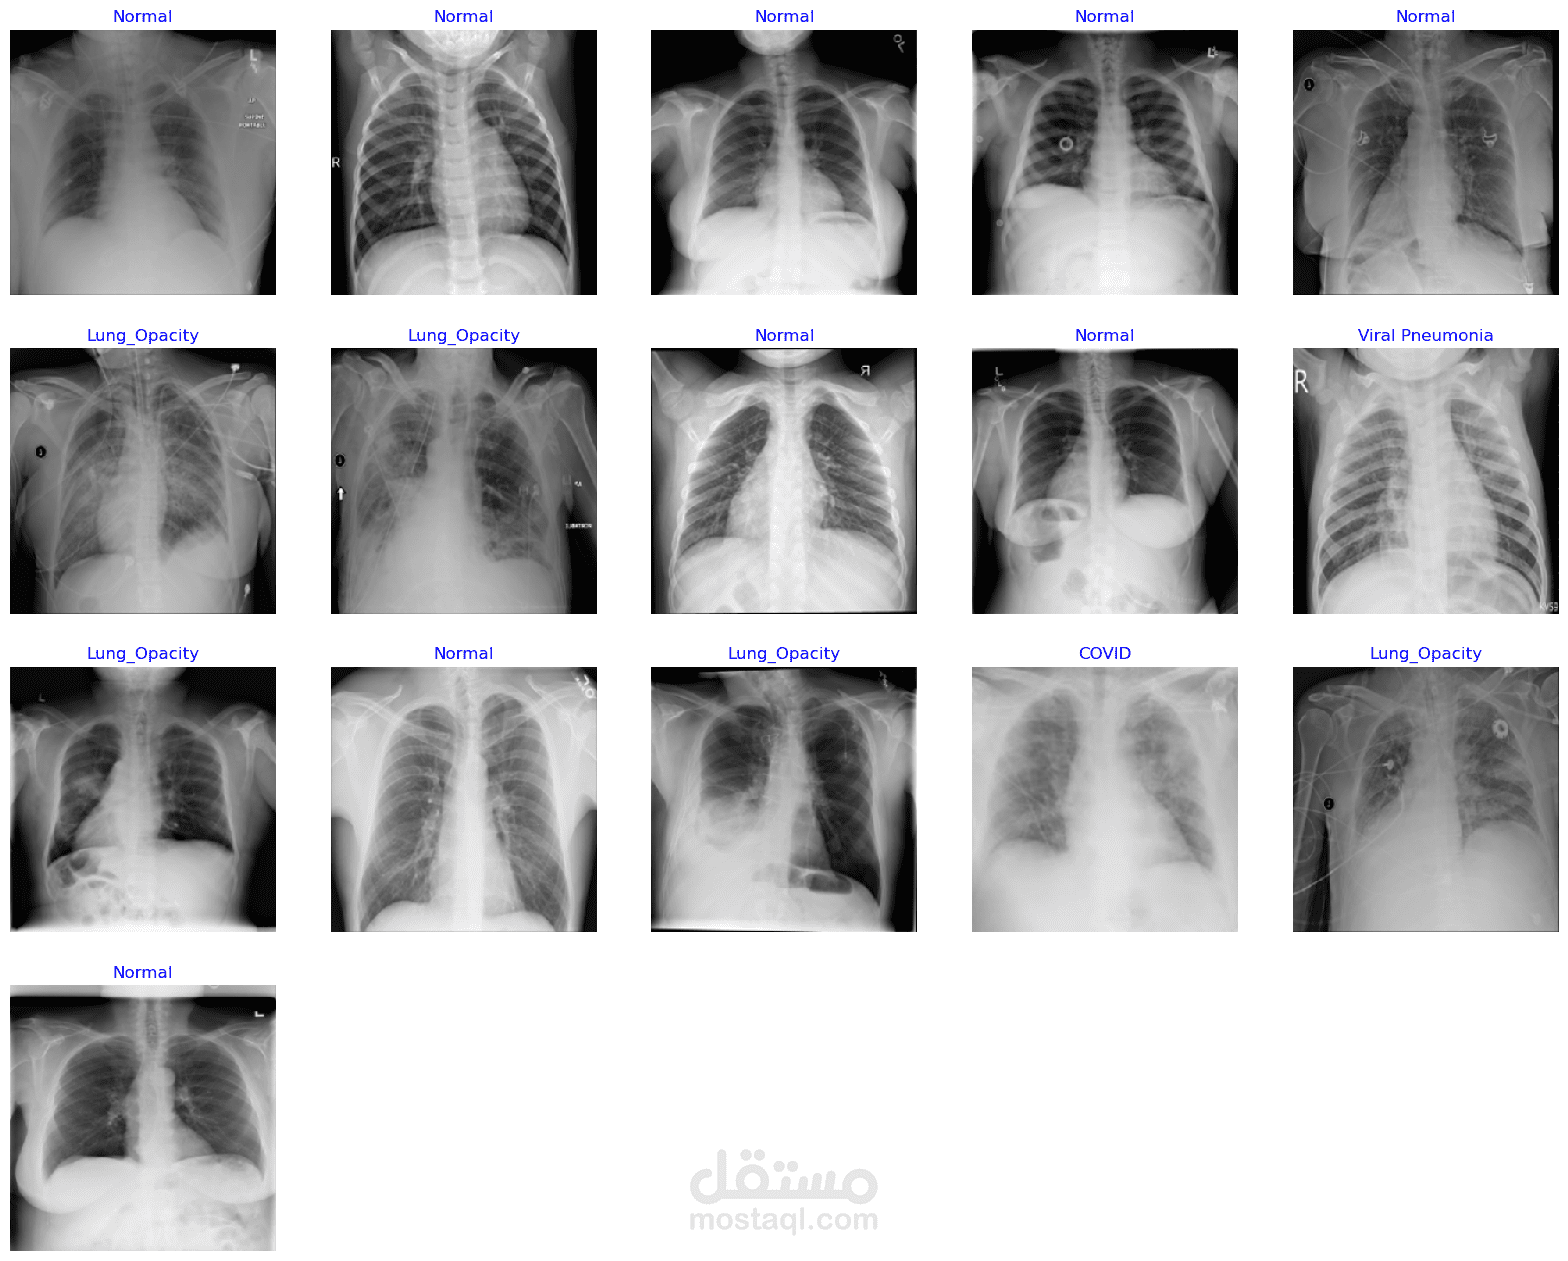

Covid-19 Radiology